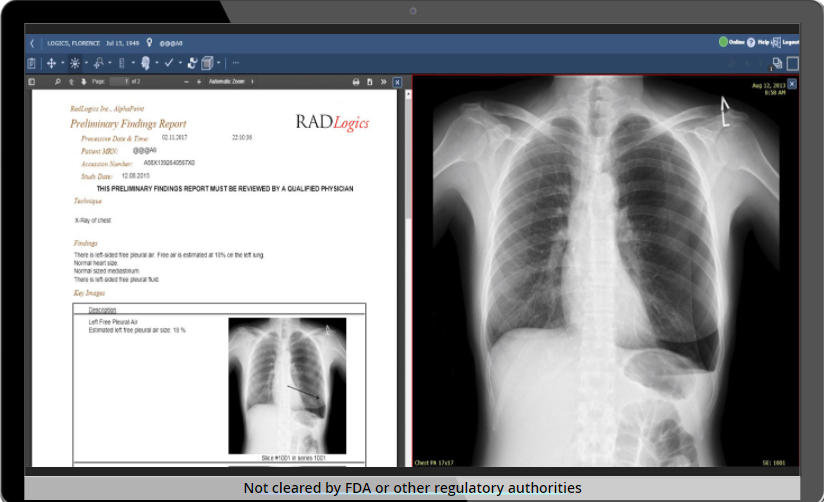

Решение Virtual Resident от RADLogic ищет, измеряет, характеризует и готовит предварительный отчет о результатах, используя анализ изображений машинного обучения для обработки огромного количества данных изображений, связанных с КТ, МРТ и рентгеновскими лучами. В течение нескольких минут черновик отчета, включающий основные изображения, доставляется в систему отчетов радиолога, что позволяет радиологам сосредоточить свое время и внимание на диагностике.

Выводы виртуального резидента объединяются с данными медицинской карты пациента. Каждая часть информации видна для просмотра и подготовки окончательного диагностического отчета, включая идентификацию пациента, метод визуализации, результаты (включая количественные измерения) и ключевые изображения. Платформа использует автоматический анализ изображений и, следовательно, не зависит от человека, что сводит к минимуму вероятность несоответствий.